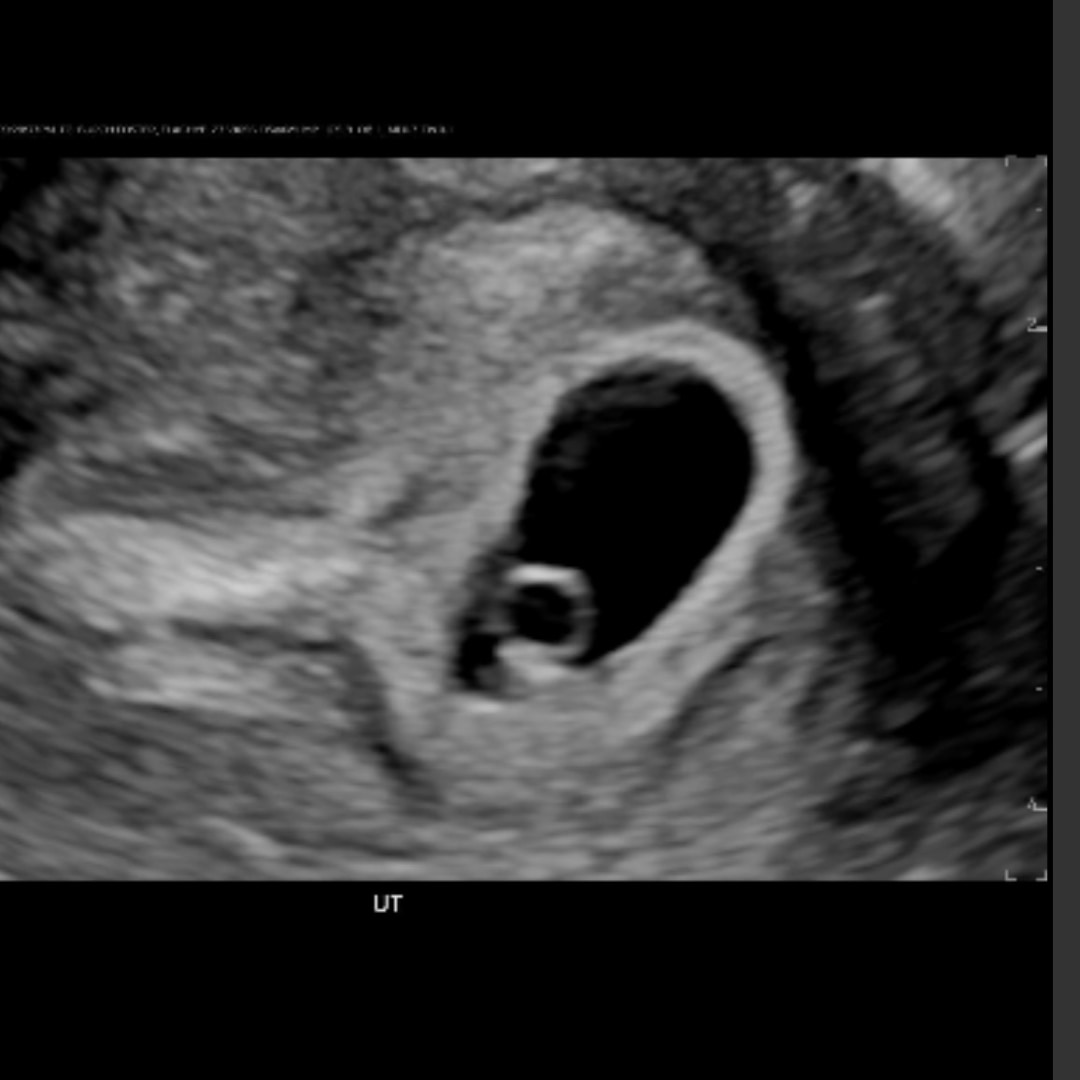

Elachye & Quariy Burch-Foster

Denver, CO

July 20, 2026

Welcome to our registry! We are so grateful for your love and support during this exciting time. We can't wait for you to meet our little one! These are some of the items we think we’ll need as our family grows. Your love means the world to us!💜💜